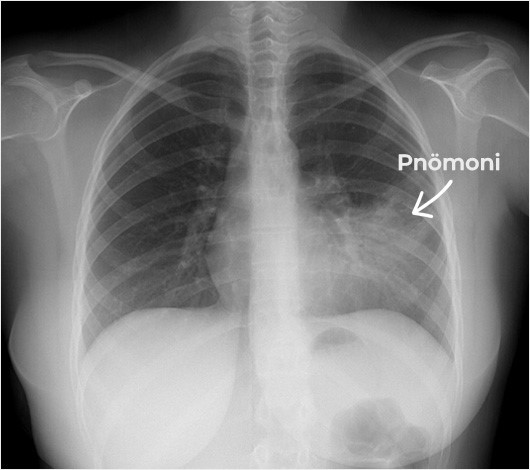

Grip, zatürre (pnömoni) ve COVID-19 bu gruba örnektir.

Enfeksiyon hastalıklarının tanısı; muayene, kan testleri, kültürler ve gerektiğinde görüntüleme yöntemleri ile konur.